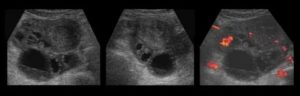

Как выглядит киста яичника на УЗИ

Основной признак кисты яичника на УЗИ – формирование на его теле полого отростка. Он отличается от нормального фолликула тем, что, на протяжении цикла, никак не меняется. К тому же, такое новообразование имеет больший размер.

На снимке УЗИ, киста яичника выглядит черным пятном, размером от 3 до 20 см.

Дермоидная

Она представляют собой одну из распространенных разновидностей патологических отростков на теле половых желез. Может иметь не только доброкачественный, но и злокачественный характер. Второе название такого образования – тератома. Возникает, преимущественно, у юных женщин детородного возраста от 18 до 30 лет.

На УЗИ, МРТ и КТ она выглядят двусторонней либо однокамерной. В 60 % случаев, тератомы содержат в своей структуре кальций. Внутри они заполнены жировой жидкостью, которая продуцируется сальной железой.

Визуально определить наличие на яичниках тератому можно по эхогенным полосам.

Геморрагическая

Такое образование представляет собой кровяной сгусток. Его структура – однокамерная, гипоэхогенная. Включения могут быть разными, например, с нитями фибрина.